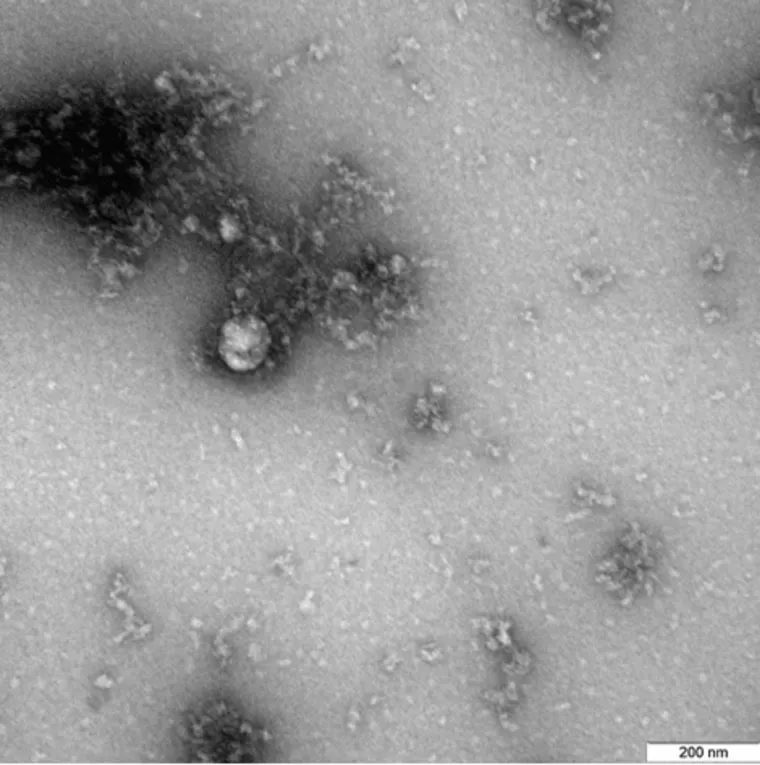

Ученые новосибирского научного центра «Вектор» впервые в мире сфотографировали «британский штамм» коронавируса. Фото опубликовано на сайте Роспотребнадзора.

«Снимок получен с помощью трансмиссионного электронного микроскопа при увеличении в 100 000 раз», — говорится в подписи к фото. На снимке видны вирусная частица (стрелка) округлой формы и типичные для коронавируса колбообразные пепломерамы (спикулы). Запечатленный штамм был выделен от пациента в декабре 2020 года. Фотография была получена в рамках продолжающегося изучения свойств данного варианта нового коронавируса. Уточняется, что мутации, характерные для британского штамма коронавируса, не сказываются на эффективности вакцины «ЭпиВакКорона».

На снимке видны вирусная частица (стрелка) округлой формы и типичные для коронавируса колбообразные пепломерамы (спикулы)